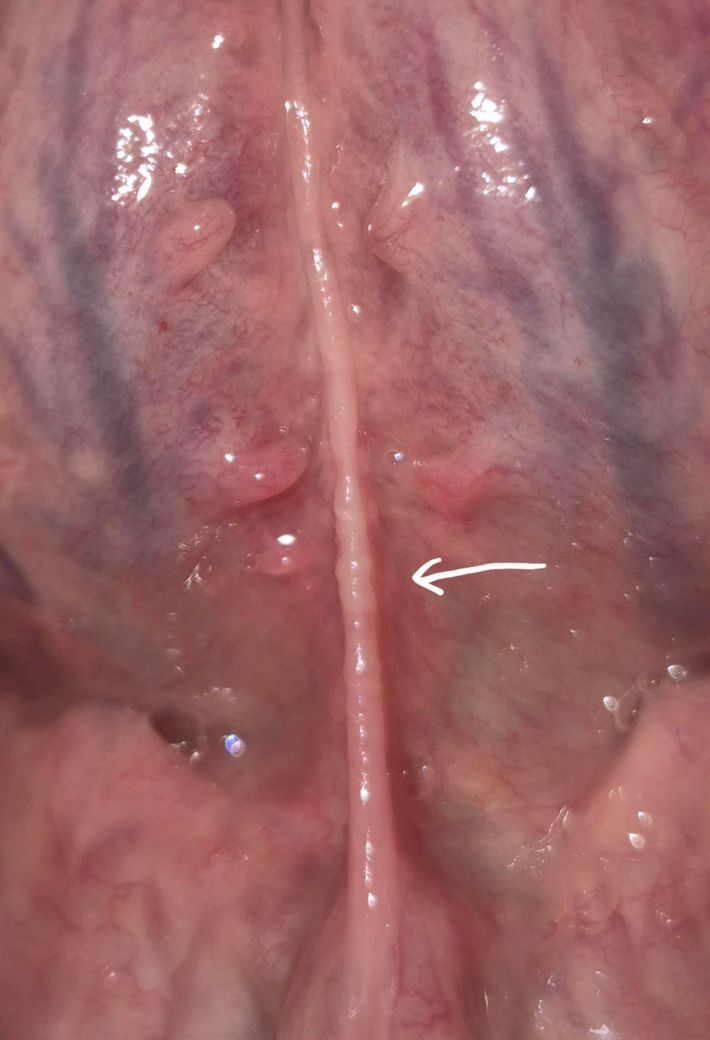

설소대 따가움+까끌까끌함 뭘까요?

설소대를 만지면 설소대가 찢어진것처럼 따가워요

촉감은 까끌까끌한 느낌입니다

피곤하면 따가웠다가 하루이틀 지나면 또 괜찮아졌다가 몇 달뒤 다시 컨디션 안좋아지면 또 따가워져요

(통증이없고 괜찮아졌을때도 설소대는 계속 저렇게 까까 끌한상태입니다)